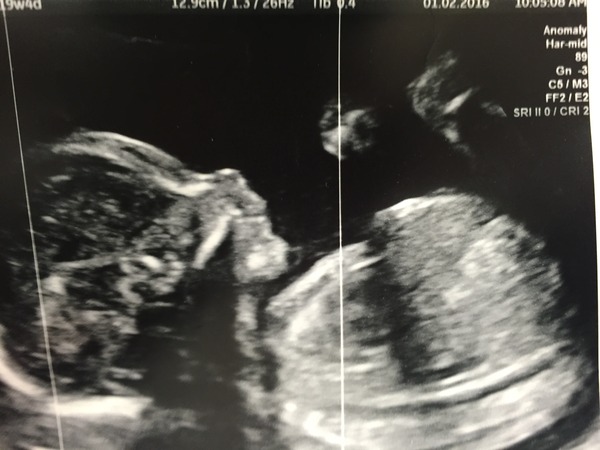

Just had 20 week scan - all good! emma no bloods or urine, just had sonographer doing a detailed ultrasound scan of baby's whole body. Charged us £5 for photo. Baby kept their legs crossed for us - so we're staying team yellow.

Your scan letter should let you know if you need a full bladder or not (think this depends what type of scan machine they have - I never needed a full bladder). Hope it goes well on Thursday for you!

All clear for my 20 week scan and still team yellow. So relieved!! Feeling even more knackered than usual as I don't think I slept at all!

jellybelly love your user name. Glad everything went well at the scan. I was told not to have a full bladder for the anomaly scan.